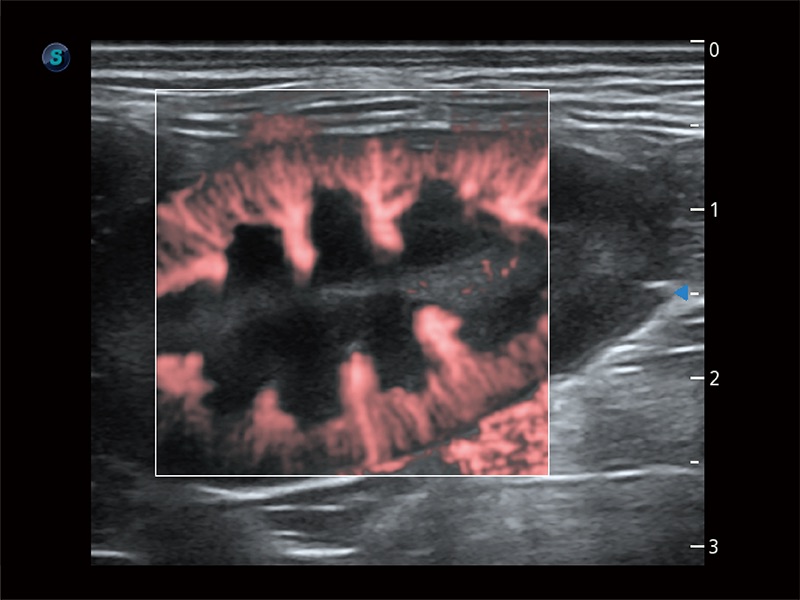

Klinisches Vertrauen verlangt hohe Leistung und fortschrittliche Werkzeuge. ProPet wurde für abdominelle und oberflächliche Untersuchungen mit fortschrittlichen Werkzeugen entwickelt, die Tierärzten in der täglichen klinischen Praxis helfen wie nie zuvor.

Die zentrale Verfolgung der Blasenwand und die Volumenmessung mittels Auto Bladder kann effizient genauere Konturen und Ergebnisse liefern, die nicht von Form und Größe der Harnblase abhängen.